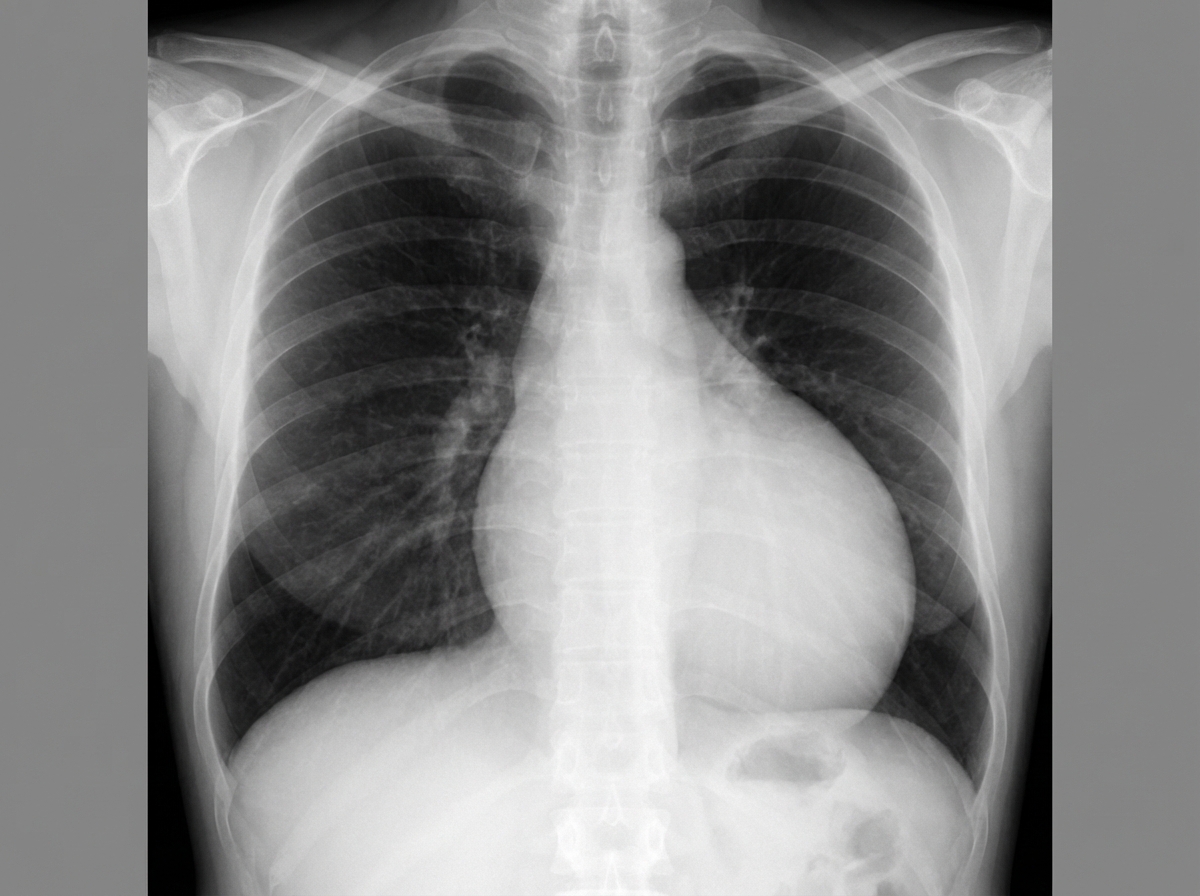

A 49-year-old man comes to the physician because of a 2-week history of increasing shortness of breath. He has also had chest pain that is exacerbated by deep inspiration. He has had recurrent episodes of pain in his fingers for the past 2 years. Two years ago, he was treated for a deep vein thrombosis. He has hypertension and anxiety. Current medications include enalapril, St John's wort, and ibuprofen. His temperature is 37°C (98.6°F), pulse is 110/min, respirations are 17/min, and blood pressure is 110/70 mm Hg. Examination shows pale conjunctiva. There is tenderness to palpation of the proximal interphalangeal and metacarpophalangeal joints of both hands. Heart sounds are distant. The lungs are clear to auscultation. Laboratory studies show: Hemoglobin 11.9 g/dL Leukocyte count 4200/mm3 Platelet count 330,000/mm3 Serum Na+ 136 mEq/L K+ 4.3 mEq/L Antinuclear antibodies 1: 320 Anti-Sm antibodies positive Anti-CCP antibodies negative An x-ray of the chest is shown. Which of the following is most likely to be seen on this patient's ECG?